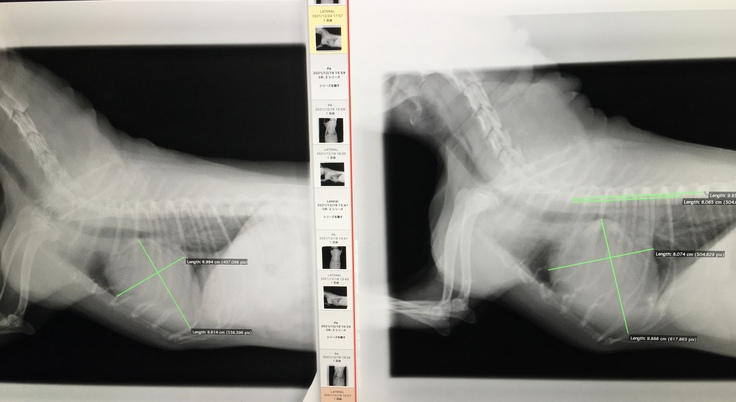

ただ、こちらの投薬治療と通院による効果はしっかりと出ており、特に膨れ上がっていた心臓が徐々に小さくなってきております。

※左が直近(12/24)、右がその約1週間前(12/19)のものです。

また、先日の診察では肺水腫も改善してきているとの事でしたので、1月23日の手術に向けての治療は順調である事、ご安心いただければと思います。